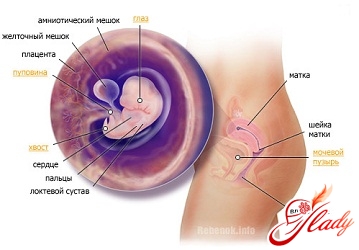

Беременность 7 неделя признаки: На данном этапе интенсивно развивается головной мозг, и происходят заметные перемены с зачатками лица, тела и конечностей ребенка. На седьмой неделе беременности у малыша уже присутствует прямая кишка и начинает формироваться грудина, тонкая кишка и пищеварительный тракт, развивается трахея, пищевод и легкие. У эмбриона по-прежнему имеется «хвостик», его не станет только к 10-11 неделе. Плацента в этот период утолщается, пуповина прикрепляется к стенке матки. Правая пупочная вена исчезает, остается только левая. Также в этот период беременности появляются зачатки глаз (радужная оболочка) и лица (носик и ротик).

Беременность 7 неделя узи: Прошла всего неделя, как появились зачатки конечностей, а уже можно догадаться, где будут плечики, а где ручки. У плода начинает формироваться личико, можно даже различить крошечные ноздри. А два крошечных пигментных кружочка, которые мы видим сбоку на головке, в течение последующих несколько месяцев переместятся на личико и превратятся в глазки.

Если у вас беременность 7 неделя, то эмбрион на этом сроке величиной с горошину: его длина приблизительно 8 мм, вес — 0,8 г.

Беременность 7 неделя симптомы: На этом этапе происходит прикрепление плодного яйца к стенке матки, которая обычно расслаблена. На седьмой неделе слизь в шейке матки, как правило, становится густой, образуется так называемая слизистая пробка, которая является барьером между маткой и внешним миром. Слизистая пробка выходит непосредственно перед самыми родами, образуя «мазню». Ореолы вокруг молочных желез могут потемнеть. Не стоит переживать — это обычное явление при беременности.